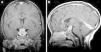

Langerhans cell histiocytosis (LCH) is a rare disease characterized by the accumulation within tissues of anomalous dendritic cells similar to Langerhans cells. The clinical presentation varies, ranging from the appearance of a single bone lesion to multisystemic involvement. Central nervous system (CNS) involvement, manifesting as diabetes insipidus secondary to pituitary involvement, has been known since the original description of the disease. Two types of CNS lesions are currently differentiated. The first, pseudotumoral lesions with infiltration by Langerhans cells, most commonly manifests as pituitary infiltration. The second, described more recently, consists of neurodegenerative lesions of the CNS associated with neurologic deterioration. This second type of lesion constitutes a complication of the disease; however, there is no consensus about the cause of this complication. Our objective was to describe the radiologic manifestations of LCH in the CNS in pediatric patients.